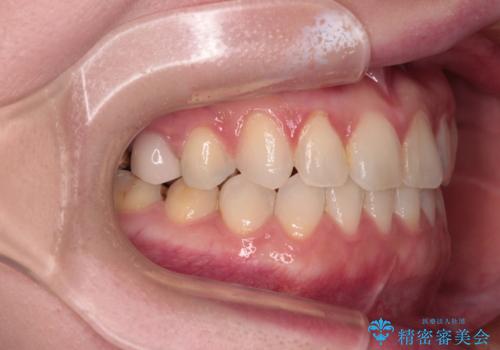

前歯のデコボコをすっきりと インビザライン矯正

- 前歯のデコボコを治したいとのことで来院された患者様です。

下顎が前方位にある方であったため、下顎の歯列全体の後方移動とIPR(歯と歯の間を削る)によってデコボコが解消するように設計し、インビザラインにより治療を行うこととしました。

装着時間が守れず、当初の予定よりも長期間必要となりました。